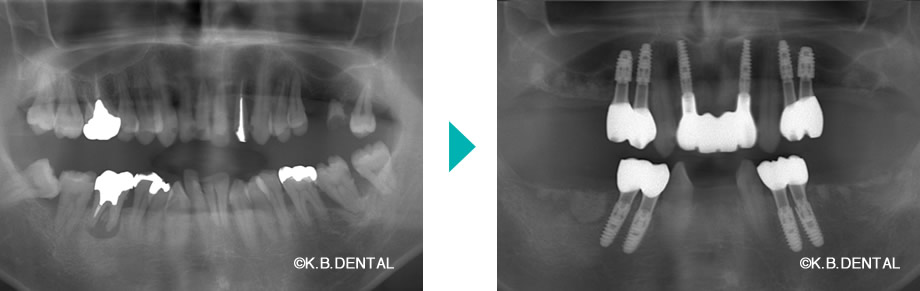

嘔吐反射改善の症例

パノラマ:嘔吐反射症例

口元:嘔吐反射症例

口腔内:嘔吐反射症例

極度の嘔吐反射で、咬合が崩壊した状態からインプラントで回復させた症例です。

嘔吐反射が著しく、奥まで歯ブラシができない場合は、状況により上下共に5番目の歯まで補綴して、ご自身でもメンテナンスしやすいように治療します。

費用:麻酔代込み総額約500万円